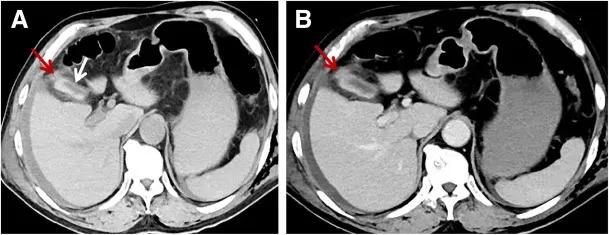

随后行腹部增强CT以进一步评估,CT图像如图A、B所示。

图A、B

CT扫描示胆囊内高密度积液,壁轻度增厚,增强差,基底“断流”,有少量游离胆囊周液(图A, B)。未见肝或脾破裂。这一结果高度提示胆囊创伤性破裂。患者随后接受胆囊切除术,胆囊底部破裂3厘米。术后病程平稳。